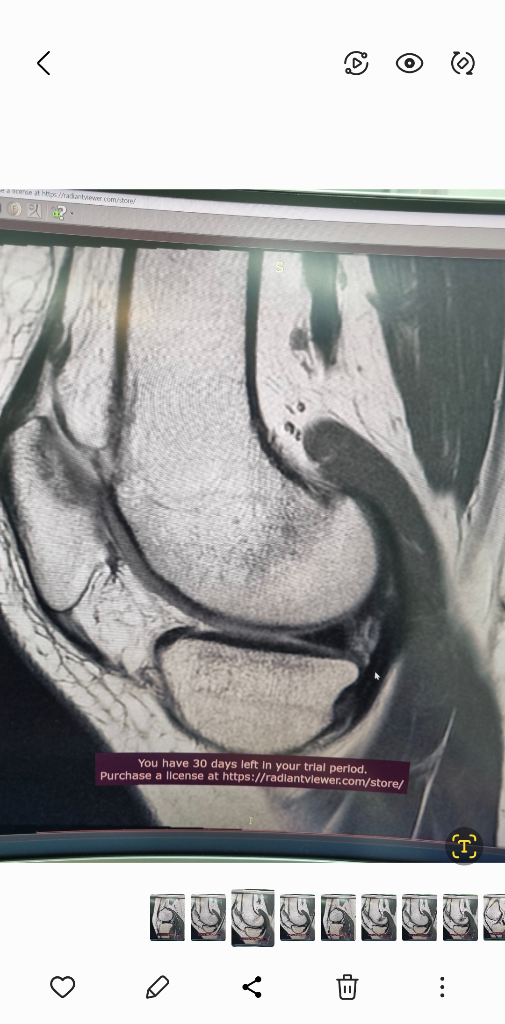

1. 추벽이 아닙니다.

2. 슬개골 관절면에 외상으로 인한 골수부종입니다.

3. 관절면 손상여부는 첨부해주신 영상만으로 알 수 없습니다